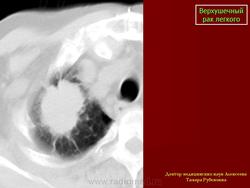

Верхушечный рак легкого

Рентгенологическую симптоматику опухолевого поражения верхушечного сегмента легкого в виде “апикального колпака” с развитием клинического синдрома, обусловленного сдавлением или прорастанием плечевого сплетения, сопровождающегося интенсивными, постоянными болями в верхней конечности и лопатке, впервые описал Pancoast H. (1924г., 1932г.).

Рентгенологические проявления верхушечного рака легкого обусловлены стадийностью его роста, при которой можно выделить 2 группы.

Первая группа: верхушечный рак без синдрома Панкоста - опухоль не выходит за пределы легочной ткани. Опухолевые узлы округлой или неправильной формы, различных размеров, однородной структуры с бугристой поверхностью и нечеткими контурами, которые в виде тяжей распространяются в прилежащие отделы легочной ткани.Может выявляться неоднородная дорожка к корню легкого в результате перибронхиального роста опухоли в сторону корня, при этом отмечается неравномерное сужение просвета сегментарного бронха.

Вторая группа: верхушечный рак с синдромом Панкоста. Клиническая картина характеризуется присоединением неврологической симптоматики различной степени выраженности. При рентгенологическом исследовании выявляется распространение опухолевого процесса за пределы легочной ткани, с вовлечением прилежащих структур средостения, мягких тканей грудной стенки, ребер и позвонков. Размеры опухолевых узлов от 3,0 см и более, имеющих округлую, овальную или неправильную форму, структура их однородная или неоднородная. Наружные контуры нечеткие, за счет распространения опухолевой инфильтрации на прилежащие органы и ткани: плевру, мягкие ткани грудной стенки, ребра, средостение, позвонки. Внутренняя поверхность опухоли может быть крупнобугристая с четкими, неровными или нечеткими контурами.